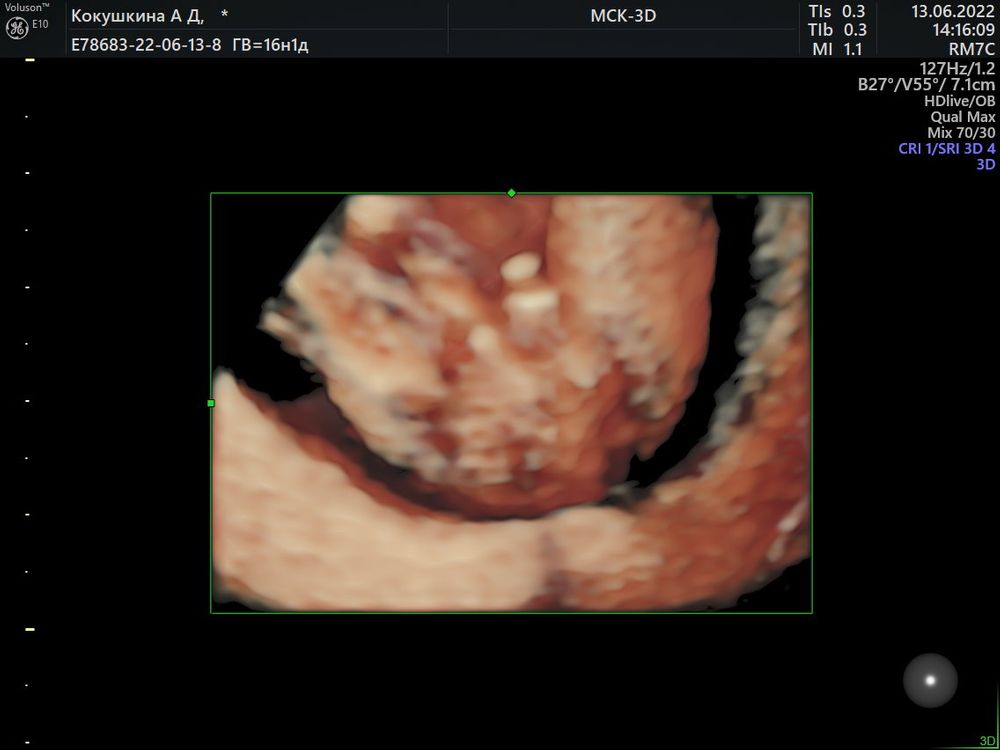

UPD: после второго скрининга стало ясно что это 100% мальчик)))

Всем привет!) предположил врач мальчика, я читала что можно по наклону пипирки понять мальчик или девочка) кто-нибудь умеет определять?) это точно не ноги, скриншот с видео, это именно то что между ног🤣 мне все таки кажется или там прям пипирка пацанская?😅